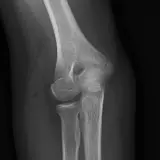

Over 2,100 interactive radiology cases, curated by radiologists for your level of training. Scroll, window, and view cases full screen — just like on PACS. Click linked findings in each writeup to jump straight to them on the image. Cases include sample reports, a focused discussion section, original illustrations, and videos.

Des cas entièrement interactifs avec les outils attendus d'un PACS — défilement, fenêtrage, zoom, déplacement, mesures, ROI et mode plein écran.

Des annotations détaillées mettent en évidence les résultats clés directement sur les cas. Cliquez sur les résultats liés dans les descriptions de cas pour accéder à leur emplacement exact sur l'examen.